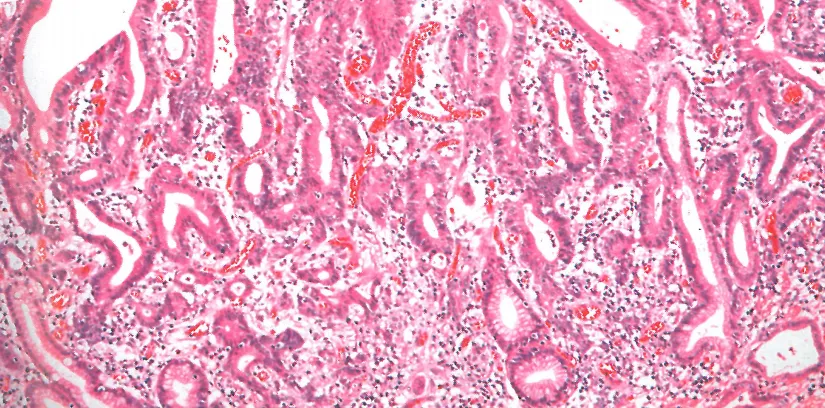

黏膜内浸润性肿瘤/黏膜内腺癌:不规则腺体,异型增生或肠化生,深层黏膜过度分支、钉状突起及单细胞浸润;即肠型高分化癌。

肠型管状腺体不规则(爬行)融合。